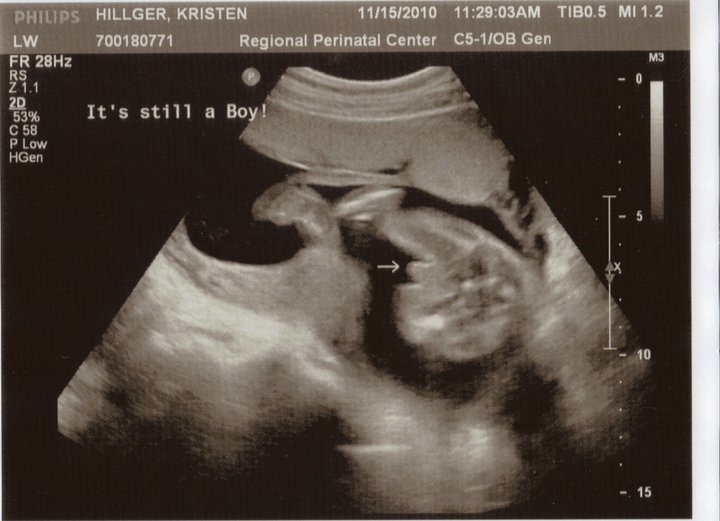

From babyultrasoundpokajire.blogspot.com

Baby Ultrasound Baby Ultrasound Quiz Ultrasound Images Quiz Sonoquizzes are a quick and easy way to test your ultrasound knowledge! This online quiz is called ultrasound image practice. They’re just for fun, but are a great way to see where you stand. It was created by member carly cristello and has 11 questions. Study with quizlet and memorize flashcards containing terms like liver,. It was created by member. Ultrasound Images Quiz.